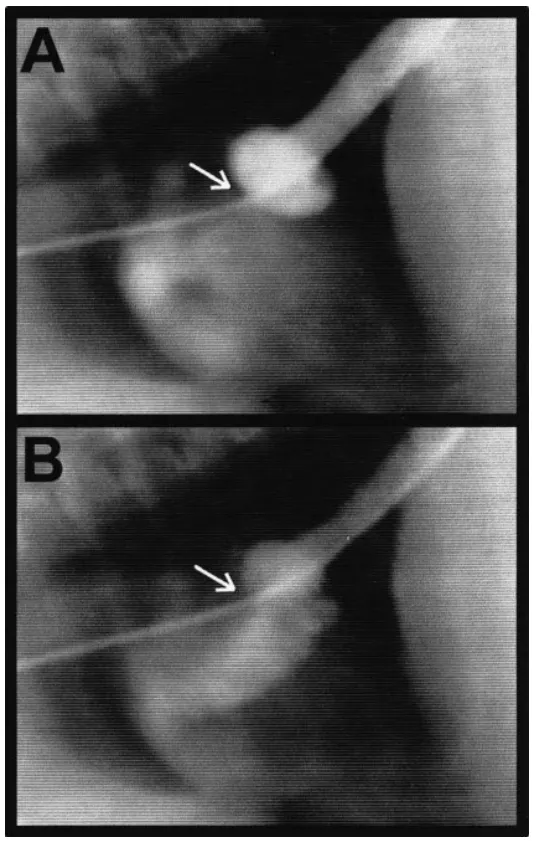

图1 右侧,短轴超声心动图视图。(A-C)扩张前。(A) 二维超声心动图显示房内膜异常(箭头)。(B) 彩色多普勒图像显示有2个区域的湍流穿过房内膜。(C) 脉冲波多普勒显示穿越心房内膜的湍流,最大速度为1.3米/秒。(D-F) 扩张后。(D) 二维超声心动图显示球囊扩张后的膜。(E)彩色多普勒图像显示球囊扩张后膜的内侧栅栏上有层流。(F) 脉冲波多普勒图像显示球囊扩张后穿过膜的层流,最大速度为1.1米/秒。RA,右心房;RV,右心室;Ao,主动脉;LA,左心房。

在第一次手术后2周,柴犬通过左颈静脉切开术进行了第二次球囊扩张。麻醉方案如前所述。平均后腔静脉压力为11mmHg,平均头颅右心房压力为2mmHg(图2 A)。血管造影再次勾勒出梗阻(图3 A)。使用经食管超声心动图引导,将导丝和直径15mm的球囊血管成形术导管放置在膜的内侧开窗处。选择15mm 球囊导管是因为在第一次手术中使用的12mm球囊导管只是暂时降低了压力梯度,可能是因为它没有撕裂膜。气球充气3次,使气球里的腰部消失了。扩张后,跨膜压力梯度为2mmHg(图2 B),血管造影显示右心房静脉流入面积增加,阻塞较少(图3 B)。第二天,彩色和脉冲波多普勒超声心动图显示几乎都呈现层流穿过膜,最大速度为1.1m/秒(图1 D-F)。此外,心房内膜看起来比扩张前更松弛更具有流动性。

图3 (A) 后腔静脉血管造影显示,球囊扩张前右心房尾部静脉回流受阻和囊状扩张。(B) 在球囊扩张后,跨膜的造影剂流动得到改善。